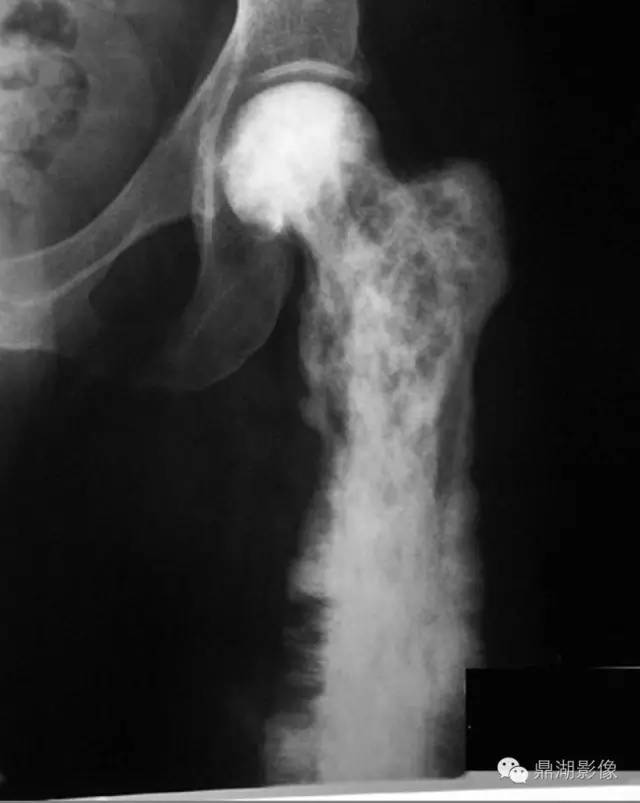

佩吉特骨病常单发也可多发,可累及全身任何骨骼,最常受累的骨骼包括颅骨、脊柱、骨盆及下肢,尤其是股骨近端。

佩吉特骨病的主要症状是疼痛,受累的长骨的骨皮质可增厚、骨干增粗,渐进或者有时出现严重的畸形,随即出现关节炎、在病变骨的凸面出现应力性骨折(尤其是股骨发生的粉笔棒断裂,chalk stick fracture)以及明显的病理性骨折。

X线可表现出病变处皮质增厚、骨增粗、溶骨和骨硬化同时存在的现象、粗糙的骨小梁等。长骨受累及早期可由一端的软骨下骨开始发病,延伸至骨干的不同部位,出现病变与正常结构的分界,如V形裂解区(“火焰”或“割草刀片”影像学改变)。负重部位的骨骼则可出现弯曲及骨皮质出现小的裂隙骨折,尤其是股骨病变时凸面的病理性骨折明显。

随着时间的推移病变可发生变化,治疗后溶骨区域可逆转。则某些特殊区域佩吉特骨病可出现特征性的改变,如脊柱受累时可出现“窗户框”现象,骨盆受累时可出现髋臼内陷及骶髂关节关节强直,颅骨受累时可出现骨质疏松性局限性钙质沉着和颅底凹陷症。